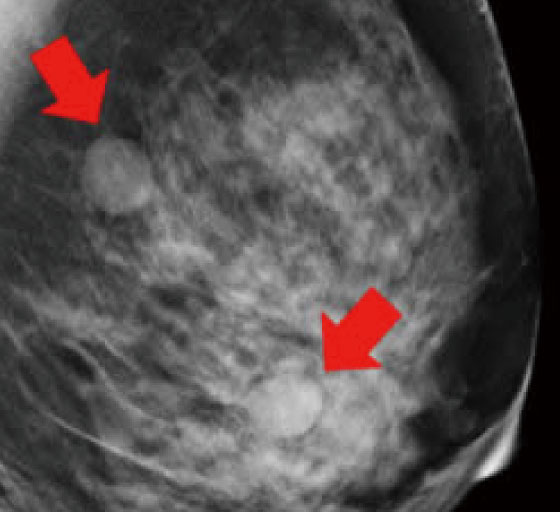

マンモグラフィでは、乳房内の腫瘤(図1)、石灰化(乳腺内にできるカルシウムの粒で、悪性、良性の場合があります)(図2)、構築の乱れ(病変による正常乳腺の構造のゆがみ)などが客観的に描出されます。

図1.腫瘤

図2.石灰化